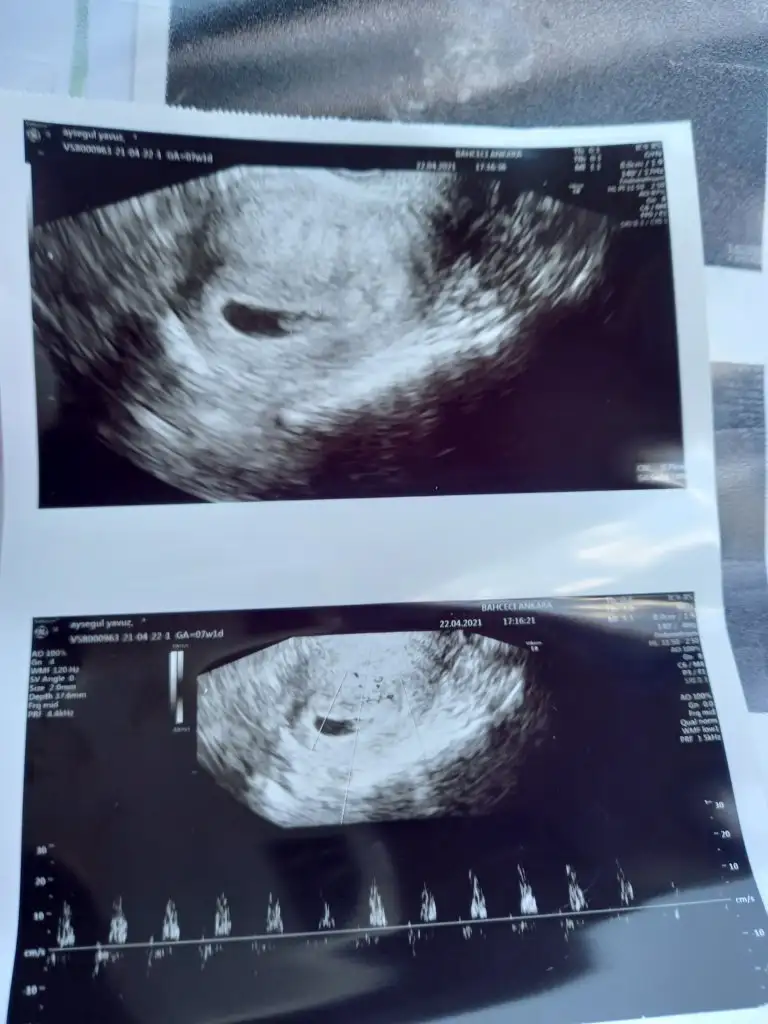

inşallah sağlıkla duymuşsunuzdur minik kalbikızlarrr benım bugun 12 bucukta kalp atısı ıcın randevum var ilk öğtendiğim gün kadar heyecanlıyım Rabbım hayırlısıyla duymamızı nasip etsin isteyen herkeze nasip etsin aratmasın ınsallahhhhh

Ya valla yoğunluktan yazamadım duyduk sukur kalp atışını hersey yolunda dedi doktorum 30 nisanda tekrar cagirdiCanm birşey yazmadın merak ettim seni

Çok sevindim canım hayırlı olsunYa valla yoğunluktan yazamadım duyduk sukur kalp atışını hersey yolunda dedi doktorum 30 nisanda tekrar cagirdi

Hayırlı olsunn sağlıkla kucağınada al inşallahYa valla yoğunluktan yazamadım duyduk sukur kalp atışını hersey yolunda dedi doktorum 30 nisanda tekrar cagirdi